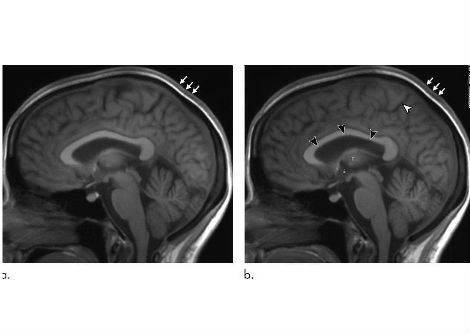

نسيج دماغ بشري مُستأصل، مُجمد بعد 100 مللي ثانية من التحفيز، يُظهر بنيةً داخلية. مقياس الشريط = 100 نانومتر.

في الدراسة الجديدة، استخدم الباحثون عينات من أدمغة فئران سليمة، بالإضافة إلى أنسجة قشرية دماغية حية أُخذت بإذن من ستة أفراد يخضعون لعلاج جراحي للصرع في مستشفى جونز هوبكنز. كانت الإجراءات الجراحية ضرورية طبيًا لإزالة الآفات من حُصين الدماغ.

ثم طبّق الباحثون أسلوب التزجيج والتجميد على عينات أنسجة دماغية من أشخاص مصابين بالصرع، ولاحظوا مسار إعادة تدوير الحويصلات المشبكية نفسه في الخلايا العصبية البشرية.